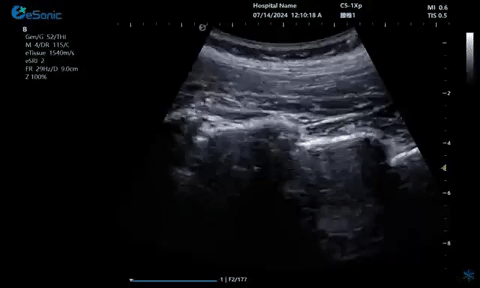

超声引导下蝶颚神经节阻滞术

大雁征-上颌动脉切面

疼痛康复领域中的肌骨超声应用,旨在实现对肌肉、肌腱、韧带、关节、神经、血管、筋膜、滑膜、滑囊、骨膜等组织结构的精确诊断评估。由于超声高频探头对上述机体组织的细微结构具有优异的分辨率,因此能够更为明确地评估这些组织的损伤和炎症状态。同时,超声设备的实时动态评估能力,使得对运动中的相关疾患也能进行准确的评估,这是其他诊断设备所不具备的优势。在康复治疗过程中,肌骨超声还用于介入穿刺治疗,如外周神经阻滞(PNB)、小关节注射、肌筋膜松解术、封闭、小针刀、冲击波治疗等。在超声引导下,这些治疗操作实现了可视化,从而真正意义上实现了精准医疗。以PNB为例,作为一种局部用药方式,其对患者全身干扰小,药物副作用少,且费用较低,因此仍然是临床治疗疼痛的主要方式之一近年来,超声技术在临床康复领域的应用日益凸显其优势。相较于传统的盲穿技术,超声引导下的PNB能够直观显示穿刺和注药过程,无需患者表达异感,避免了反复穿刺给患者带来的痛苦。这种技术显著提高了外周神经阻滞、静脉穿刺的成功率、精确性和安全性,同时减少了不良反应和并发症的发生,为患者带来了福音也相信在不久的将来,eHertz系列产品将会在全球医疗市场上掀起一场技术革新的风暴,让更多的人受益于我国医疗技术的进步。